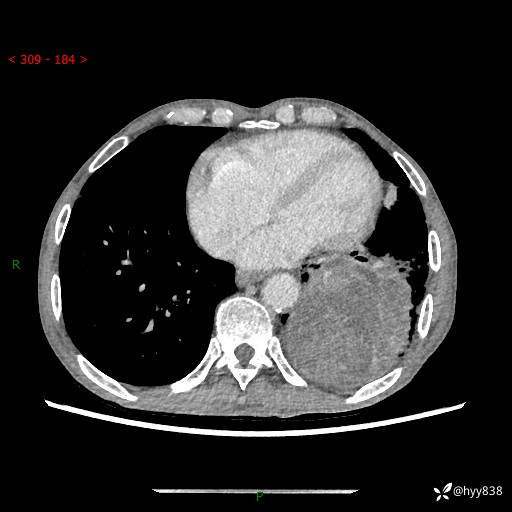

77岁/男,腹痛2月,CT发现左肺占位1天。巨大肿块,肺内或肺外来源…结果公布~

主诉:腹痛2月,CT发现左肺占位1天

现病史:患者于2025年9月间断左下腹胀痛,在当地镇卫生院行彩超检查考虑泌尿系结石,行止痛排石对症治疗未见明显好转;1天前腹痛症状加重,至当地市第三人民医院行CT检查:左肺下叶巨大团块状软组织影,考虑肿瘤性病变,建议增强CT检查;左侧胸腔积液;纵膈内淋巴结肿大;双肺肺气肿;右肺中叶纤维灶。为进一步求治,来我院就诊。

胸部CT平扫+增强